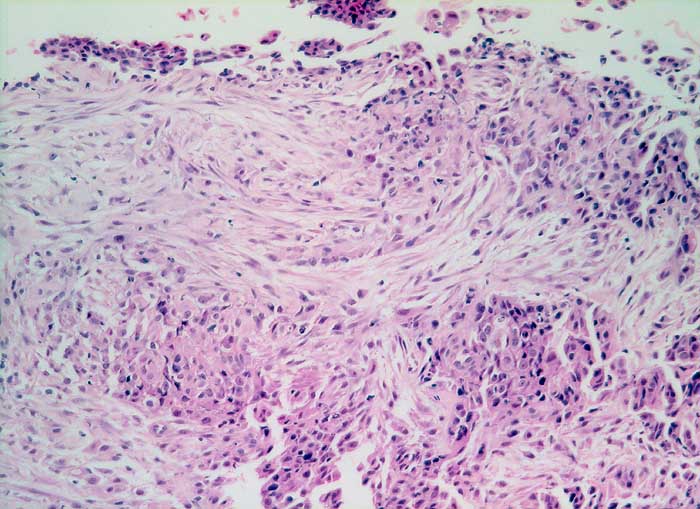

Entscheidend für die Diagnose eines malignen Mesothelioms sind maligne Zellen, die aussehen wie Mesothelzellen. Typisch ist ein Kontinuum von gutartigen, abnormen und malignen mesothelialen Zellen. Die Tumorzellen bilden polyzyklisch begrenzte papilliforme Verbände oder sitzen einem homogenen Matrixkern auf. Zellkannibalismus und lange Zellketten (Indian Files) sind häufig bei Mesotheliomen und selten in gutartigen Ergüssen. Die einzelnen malignen Zellen sind grösser und variabler als gutartige Mesothelien. Oft trifft man auf grosse und mehrkernige Tumorzellen. Das Zytoplasma von Mesotheliomen ist auffallend dicht ,anders als das eher helle Zytoplasma von Adenokarzinomen.